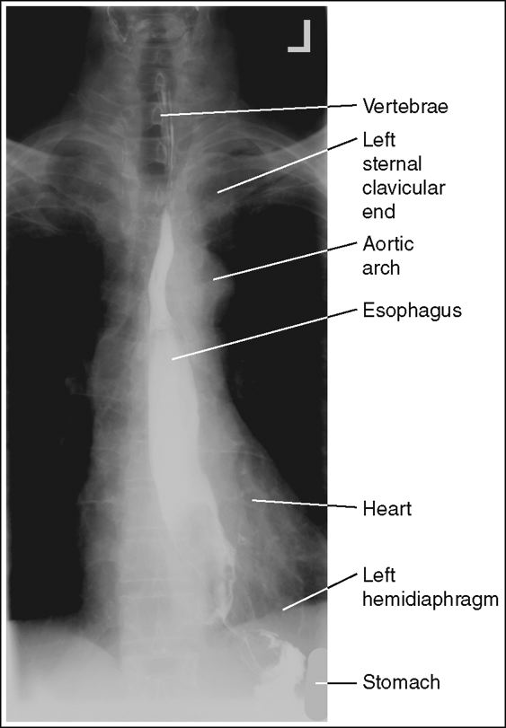

PA Esophagus with Proper positioning

PA Esophagus with Left shoulder rolled up